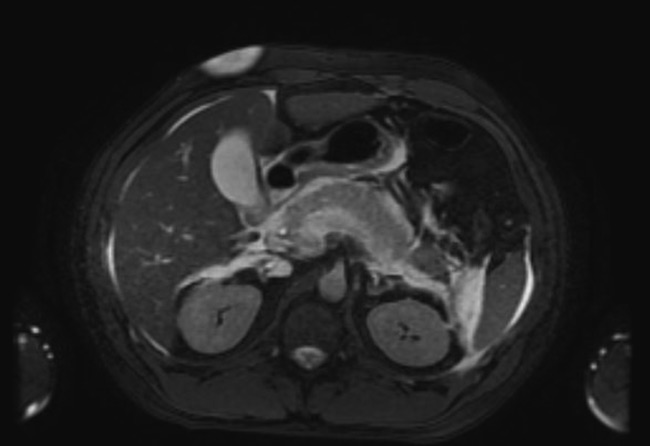

The patient’s symptoms worsened over the course of admission. The lipase level continued to rise and reached 5156 U/L on day 2 of admission. Findings of a follow-up CT scan of the abdomen (Figure 2) and magnetic resonance cholangiopancreatography (MRCP) (Figure 3) were consistent with severe pancreatitis.

Figure 3. MRCP showing increased peripancreatic fluid consistent with progressed severe pancreatitis. No choledocholithiasis, biliary stricture, or biliary duct dilation were noted.